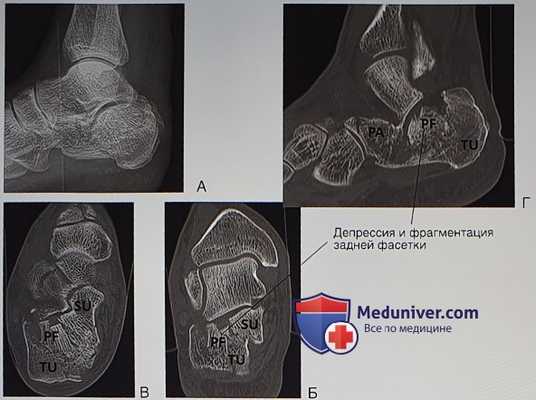

Рисунок 1 Рисунок 2. Косая первичная линия перелома и вторичная линия перелома, формирующие основные подлежащие репозиции фрагменты пяточной кости. PF — наружная часть задней фасетки, сочленяется старанной костью; SU - опора таранной кости (включает внутреннюю часть задней фасетки); TU - пяточный бугор.

- Выполняется рентгенография обеих пяточных костей и стоп в боковой проекции. На рентгенограмме в боковой проекции можно увидеть перелом пяточной кости в сочетании с появлением двойного контура на уровне подтаранного сустава или ниже него, уплощение угла Бёлера, составляющего в норме 25-40°, и исчезновение нормального наклона пяточной кости (рис. 1). Если подозревается перелом пяточной кости или этот перелом виден на рентгенограмме в боковой проекции, назначается компьютерная томография, необходимая для точной оценки характера перелома и выбора наиболее подходящего плана лечения (рис. 2). Другие рентгенологические проекции назначаются по показаниям: проекция по Harris позволяет увидеть перелом в области задней фасетки, расширение пяточной кости с формированием импинджмента наружной стенки и снижение высоты пяточной кости. На рентгенограмме в тыльно-подошвенной (передне-задней) проекции с наклоном рентгеновской трубки до 20° можно увидеть перелом в области пяточно-кубовидного сустава. Передне-задняя проекция по Broden при внутренней ротации стопы на 45° и подошвенном сгибании под углом 10-40° позволяет оценить смещение задней фасетки и используется интраоперационно для контроля качества репозиции

Рисунок 3. Передний отросток (РА) - это четвертый фрагмент пяточной кости. Он может раскалываться продольно, образуя пятый, переднемедиальный, фрагмент. SU — фрагмент опоры таранной кости; TU — пяточный бугор.

2. Компьютерная томография:

- Исследование выполняется с шагом 1 мм и построением следующих реконструкций:

• Перпендикулярно задней фасетке для визуализаций диастаза или депрессии и обнаружения постоянного фрагмента пяточной кости, включающего опору таранной кости (рис. 3, А-Б)

• Параллельно плоскости пола для получения срезов, перпендикулярных пяточно-кубовидному суставу (рис. 3, В)

• В сагиттальной плоскости для оценки ориентации фрагментов перелома задней фасетки (рис. 3, Г)